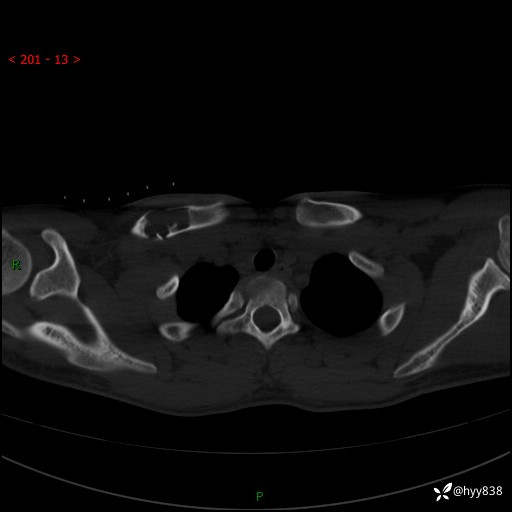

CT